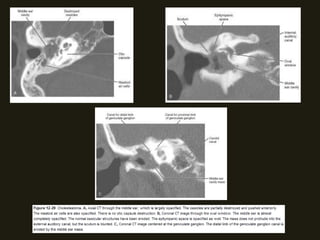

SCHWANOMAS ACÚSTICOS

• Tumores benignos do VIII PC ocorrem no CAI/ângulo

cerebelopontino, surgindo na junção das células da glia com

as de Schwann; Associação com neurofibromatose tipo 2;

• Sintomas dependem da localização do tumor (há compressão

dos nervos coclear e vestibular (CAI) – zumbido, diminuição

acuidade auditiva;

• RM método de escolha (nervo espessado e com realce pelo

contraste; podem ser císticos;); diferencia schwanomas

pequenos dos nervos normais;

NEOPLASIAS BENIGNAS

• Podem ser massas pequenos ou grandes;

• Grandes – distorção da fossa posterior; hérnia de tronco,

hidrocefalia e compressão do IV ventrículo;

• TC alta resolução – mostras alterações ósseas do CAI, porus

acusticus e cápsula óptica; Assimetria dos CAI > 2mm sugere

MASSA!!